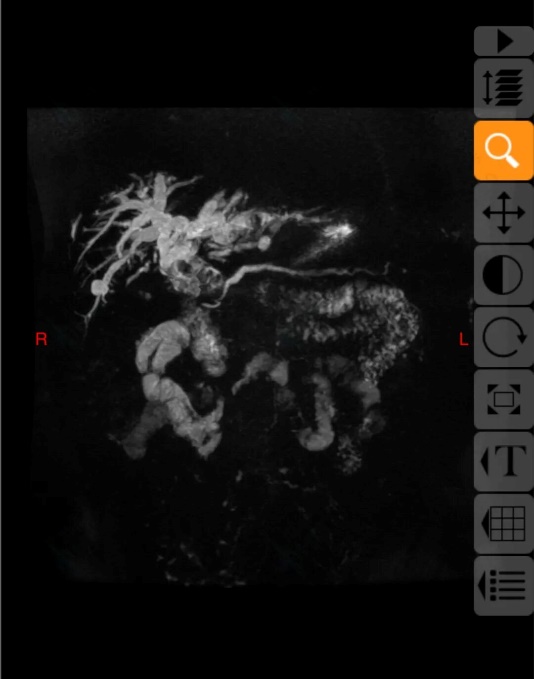

前几日,患者在当地医院复查上腹部CT,结果提示“胆总管结石、肝内胆管结石”。为求进一步诊治,患者慕名来到东院区肝胆外科就诊,以“胆总管结石”将其收治入院。因患者病情复杂、手术史特殊,科室高度重视,沙焕臣主任组织科室骨干力量多次进行病情讨论及全面术前评估。医疗团队在系统分析患者历次手术资料及最新影像学检查后指出,患者因多次手术导致腹腔广泛粘连、解剖结构紊乱,同时肝内胆管结石位置高、分布广泛,若采用传统手术方式,不仅难以彻底清除结石,也无法有效解决胆汁引流问题,手术难度及风险极高。

10月17日,在麻醉手术部团队的密切配合下,沙焕臣主任主刀手术,术中发现腹腔内粘连严重,肠管、大网膜与腹壁、肝脏广泛致密粘连。手术团队精细操作,逐步分离粘连,成功显露肝门区及胆总管。随后在胆道镜辅助下,彻底清除胆总管及部分肝内胆管结石。针对左肝外叶多发结石伴局部胆管狭窄的情况,团队实施了肝左外叶切除,并对高位胆管进行精细修补与成形,最后顺利完成胆肠吻合术,重建胆汁引流通道。手术过程顺利,术中出血量控制良好,患者生命体征平稳,术后患者安全返回病房。在护理团队的精心照护下,患者恢复进程良好,未出现胆漏、出血、感染等并发症,目前已顺利过渡到流质饮食阶段,并开始逐步下床活动,身心状态稳步改善。